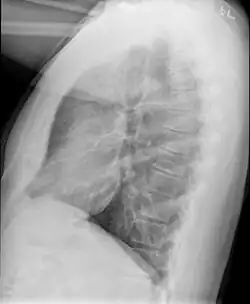

Example of early disease with mild flattening of the diaphragm

Bronchiolitis obliterans is often diagnosed based on the symptoms of obstructive lung disease following lung injury. The definitive diagnosis is through biopsy, but due to the variable distribution of lesions, leading to falsely negative tests, and invasive nature of this procedure it is often not performed.[6][11] Several tests are often needed to diagnose bronchiolitis obliterans, including spirometry, diffusing capacity of the lung tests (DLCO), lung volume tests, chest X-rays, high-resolution CT (HRCT), and lung biopsy.[11][4]